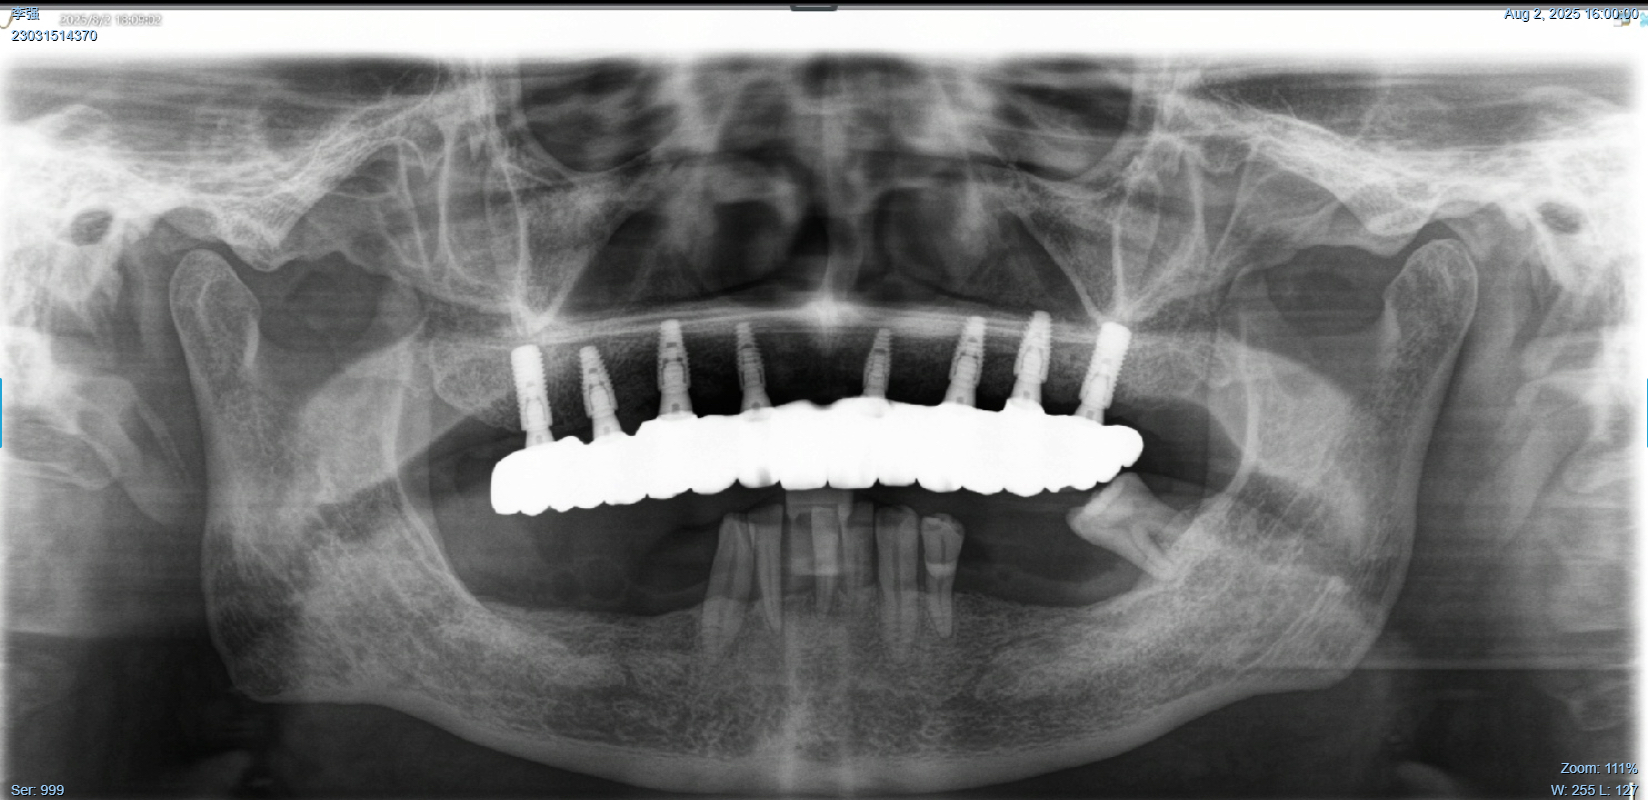

该患者就是因牙周病导致牙齿松动脱落,我们通过在半口牙槽骨上植入8颗种植体,然后在种植体上安装连桥牙冠,从而恢复半口牙齿的咀嚼功能和美观。相对于传统的种植修复方式缺一颗种一颗。4-8颗种植体的种植手术创伤相对较小,大大的减少了患者的疼痛感。

种植牙是当前缺牙修复的理想选择,但成功与否依赖医生技术、患者自身条件和术后维护。尽早修复缺牙,才能避免邻牙倾斜、咬合紊乱等问题,重获健康笑容